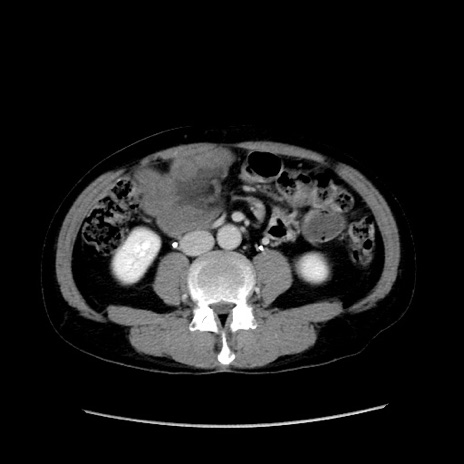

症例37(横断像)

【症例】40歳代 男性

【主訴】腹痛

【現病歴】4時間ほど前に電車に乗車中に臍部上より腹痛出現。徐々に増悪し起立困難となり、救急外来受診。生ものは数日食べていない。今朝お雑煮を食べた。

【身体所見】BT 36.8℃、BP 117/84mmHg、HR 91/min、SpO2 97%、苦悶様、腹部:臍上部広範囲圧痛あり、反跳痛±

【データ】WBC 8100、CRP 0.03